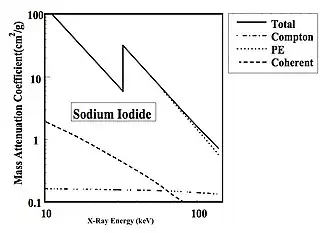

K-Edge Effect

- A final material to consider is sodium iodide - see Figure 3.8. This material is widely used in radiation detectors and its attenuating properties are quite similar to those of iodinated contrast media. This material is also of interest because it demonstrates an interesting absorption phenomenon, that of a K-absorption edge. This happens when the energy of the incoming X-rays exceeds that of the K-shell of the iodine atoms, so that these electrons can now be ejected from the atom.

- The Photoelectric Effect is again seen to decrease with X-ray energy, but this time with an absorption edge at about 33 keV. The Compton Effect is again seen to be constant at ~0.2 cm2/g, while Coherent Scatter, although more prominent, once again falls off with increasing X-ray energy.

- Note also that the total attenuation in sodium iodide is about 10 times greater than cortical bone at low X-ray energies while it is about 30 times greater (and about 300 times that of muscle) at just above the K-absorption edge. This characteristic has made this material suitable as a radiation detector. It is also one of the reasons why contrast media containing iodine are used to distinguish blood vessels from surrounding tissues in angiography.

- A final point to note is that numerous materials have been found which have K-absorption edges in the diagnostic energy region. These include cesium iodide, where in addition to the iodine K-edge, there’s a second one at 36 keV due to the cesium atoms. Lanthanum, as another example, has a K-edge at 39 keV - and we saw its effect on the X-ray energy spectrum earlier. These materials have found application in intensifying screens because of this absorption feature.

- Another example is barium, which has a K-edge at 37 keV. This characteristic has found application in barium contrast media used, for example, to distinguish the digestive tract from the surrounding tissue in the Barium Meal. It has also found application in computed radiography (CR) where the photostimulable material is made from barium fluorohalide.